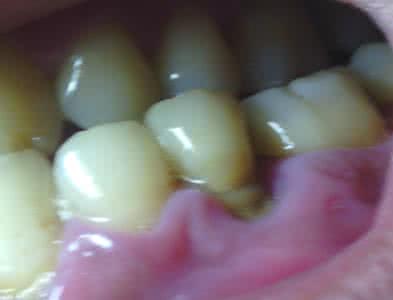

儿童牙龈炎症状图片

儿童牙龈炎症状图片,儿童根尖周炎脓包图片

儿童牙龈炎

儿童牙龈炎症状

牙龈炎症状图片

宝宝牙龈炎症状图片

牙龈炎图片早期症状

牙龈炎症状图片轻微